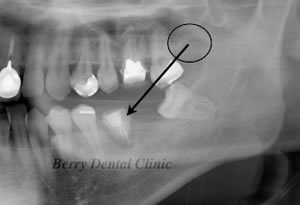

黒色の丸印から1の親知らずが移植されました。

今度は丸印の部分の下の親知らずをすぐ前の位置に移植しました。

矢印の部分に少し拒絶反応が認められますが、患者さんは痛くなく腫れもないので問題なく食事ができるという事でそのまま様子を見ています。